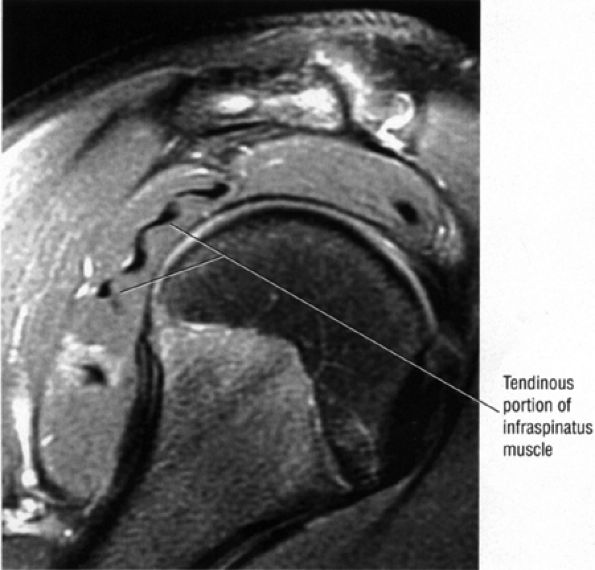

The infraspinatus muscle (Fig. 8.100) is bipennate and has a median raphe,74 which at surgery may be mistaken for the border between the infraspinatus and teres minor.

FIGURE 8.100 ● The bipennate infraspinatus muscle.